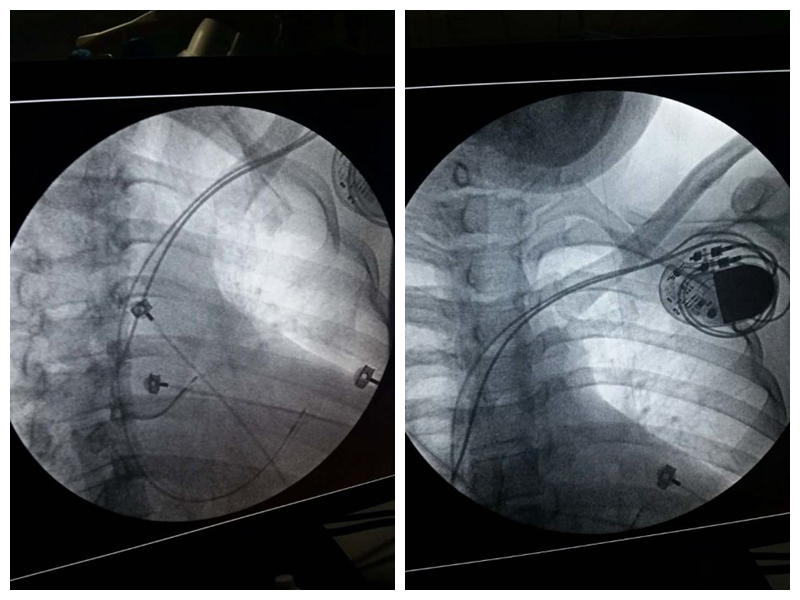

【新业务 新技术】心内科成功实施永久性双腔心脏起搏器植入术

2月19日下午,我院心内科二病区蔡文平主任带领科室医护团队,在兰大二院吴强主任的全程指导下,为一位完全性房室传导阻滞致反复心源性晕厥的危重患者成功植入永久性双腔心脏起搏器,并再次完成一例严重冠脉病变者行PTCA后成功植入冠状动脉内支架。

据悉,心内科二病区自分设病区以来,在稳步推进冠脉介入治疗的同时,全科室同仁团结进取,借助省内外知名专家的优质资源,积极有序的逐步开展心脏电生理专业诊治新业务,打开了专业发展的新局面。目前,蔡文平主任已与多名行业内专家就我院心脏起搏器植入及心律失常射频消融治疗等业务的开展达成了良好的协作意向,为我市心脏电生理诊治的发展翻开了新篇章,这一举措也将造福于我市广大心律失常患者,为他们带来最便利、尖端的专业诊疗服务!